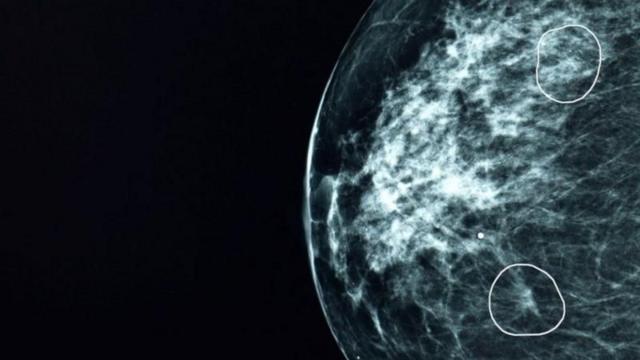

செயற்கை நுண்ணறிவு கருவி

படக்குறிப்பு,

மியா(MIA) எனப்படும் கருவியால் மருத்துவர்கள் தவறவிட்ட கட்டிகளைக் கண்டறிய முடிந்தது.

பிரிட்டிஷ் மருத்துவமனைகளில் பரிசோதிக்கப்பட்ட ஒரு செயற்கை நுண்ணறிவு (AI) கருவி, மருத்துவர்களால் கவனிக்கப்படாமல் போன 11 பெண்களில் மார்பக புற்றுநோயின் சிறிய அறிகுறிகளை அடையாளம் கண்டுள்ளது.

மியா(MIA) என்று அழைக்கப்படும் இந்தக் கருவி, பிரிட்டனில் உள்ள பல சுகாதார மையங்களில் சோதிக்கப்பட்டது. இந்த கருவி கிட்டத்தட்ட 10,000 மேமோகிராம்களை பகுப்பாய்வு செய்தது.

அவற்றில் பெரும்பாலானவை புற்றுநோயின் அறிகுறிகளைக் காட்டவில்லை. ஆனால் மருத்துவர்களால் கண்டறியப்படாத 11 நோயாளிகளை அந்தக் கருவியால் வெற்றிகரமாக அடையாளம் காண முடிந்ததுள்ளது.

ஆரம்ப கட்டங்களில், புற்றுநோய்கள் மிகவும் சிறியதாகவும், அடையாளம் காண்பது கடினமாகவும் இருக்கும்.

மனிதக் கண்ணுக்கு தெரியாத அத்தகைய கட்டிகளை, செயற்கை தொழில்நுட்பக் கருவியால் சுட்டிக் காட்ட முடிந்தது.